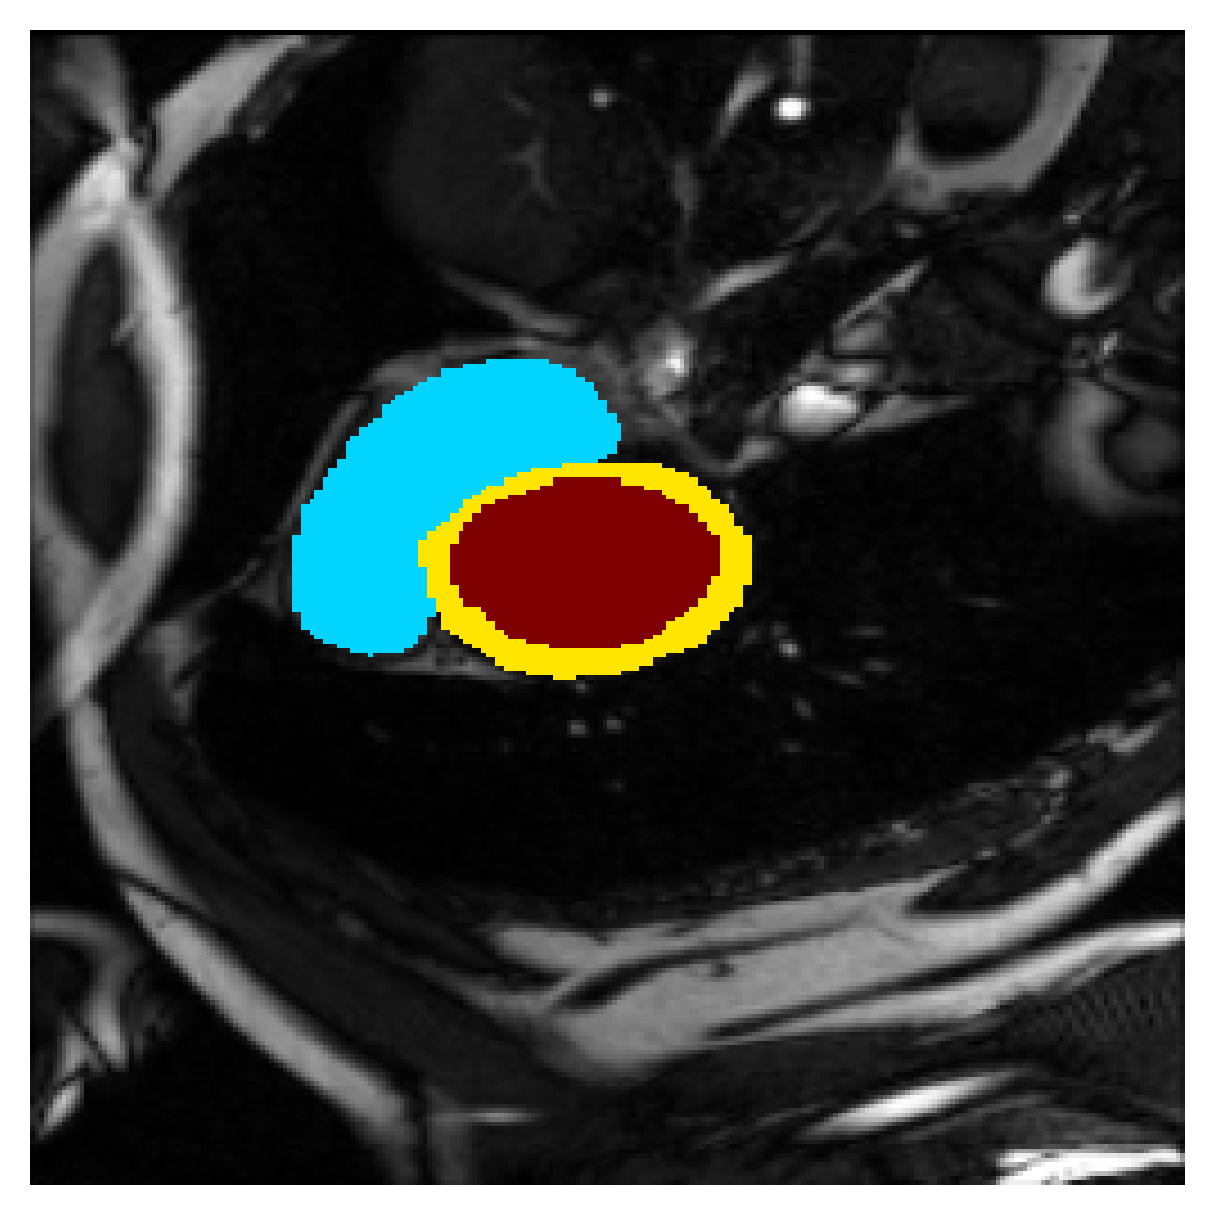

5.1 Segmentation of cardiac structures

The average 3D Dice scores and HD95 values on the ACDC test set are given in Table 2, and boxplots in figures 4 and 5 show the distributions. We see that, in terms of DSC, the proposed strategy of using intensity-aware distances withing boundary loss performs better than simply using the Euclidean distance, with the best results achieved by using the strictly intensity based MBD. The HD95 however favors the original version of , which may be do to its smoother predictions and less fragmentation and oversegmentation. The CRF-loss results are significantly worse in both metrics.

In Figure 3 we show the 3D DSC validation curve evolution for a single run. The CRF-loss seems to have converged to a low DSC value, while all settings combining CE and boundary loss reach values close to the full supervision in the beginning of the training and then slowly collapse towards to the point annotations. The MBD version stands out, degrading slower, thus providing a wider range of potentially good models for evaluation.

Qualitative comparison

In Figure 6 we provide qualitative results on a number of randomly chosen test set slices. Upon visual inspection, we can observe that training with the intensity-aware distances (particularly with and ) follows the image gradients better and is better at recovering the underlying shape than the Euclidean version. The CRF-loss seems to recover the shape of the myocardium and left ventricle to some extent, but fails entirely on the right ventricle.